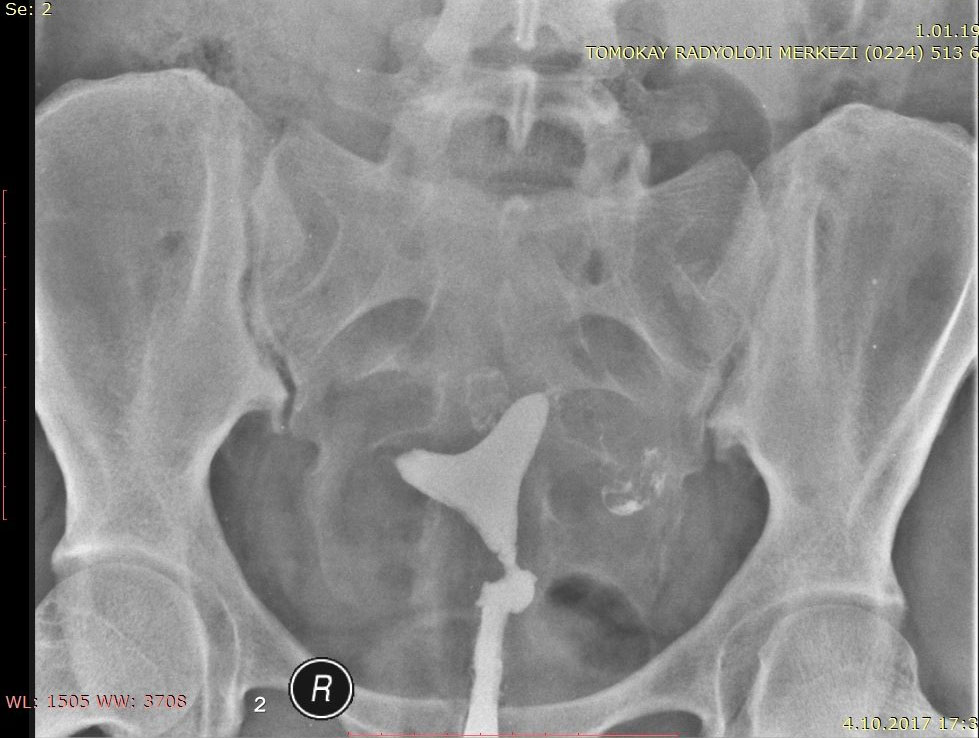

GELİŞİMSEL KALÇA ÇIKIĞI (GKÇ)

Doğuştan kalça çıkığı, doğumsal kalça çıkığı, DKÇ gibi isimlerle bilinen bu hastalığa en doğru ismiyle Gelişimsel Kalça Çıkığı diyoruz. Kesin teşhis sadece Kalça Ultrasonu ile yapılabilmektedir. İlk 3-4 ayda teşhis edilir ise başarılı bir tedavi ile sağlığına kavuşmaktadır.